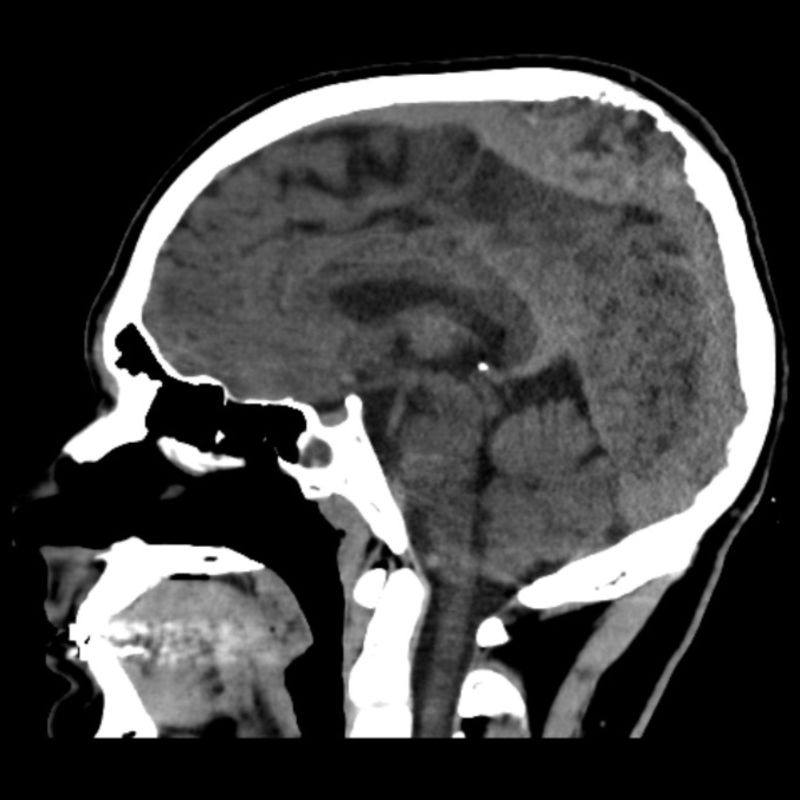

- A) Vertekste, orta hatta, multikistik, T2A sekanslarda yoğun içerikli sıvı-sıvı seviyelenmesi (oklar) ve T1A sekanslarda hiperintens, SWI sekanslarda blooming artefaktı oluşturan, belirgin düşük ADC değerlerine sahip, kanama alanları içeren (oklar) kitlesel lezyon mevcuttur.

- B) Parietal kemik iç tabulada erozyon (oklar), süperior sagital sinüste inferiora yer değiştime ve invazyon (oklar) ve lezyonda heterojen kontrastlanma izlenmektedir.

- MR görüntülemede genellikle T1 ağırlıklı görüntülerde gri cevher ile izointens, T2 ağırlıklı görüntülerde hiperintens, heterojen kontrast tutulumu gösteren kitlesel lezyon izlenir. Nekrotik, hemorajik, kistik alanlar içerebilir. Kanamaya bağlı sıvı-svı seviyeleri izlenebilir.

- İntrakraniyal uzanımı bulunan lezyonlarda dural kalınlık artışı ve komşu parankimde perilezyoner ödem izlenebilir.